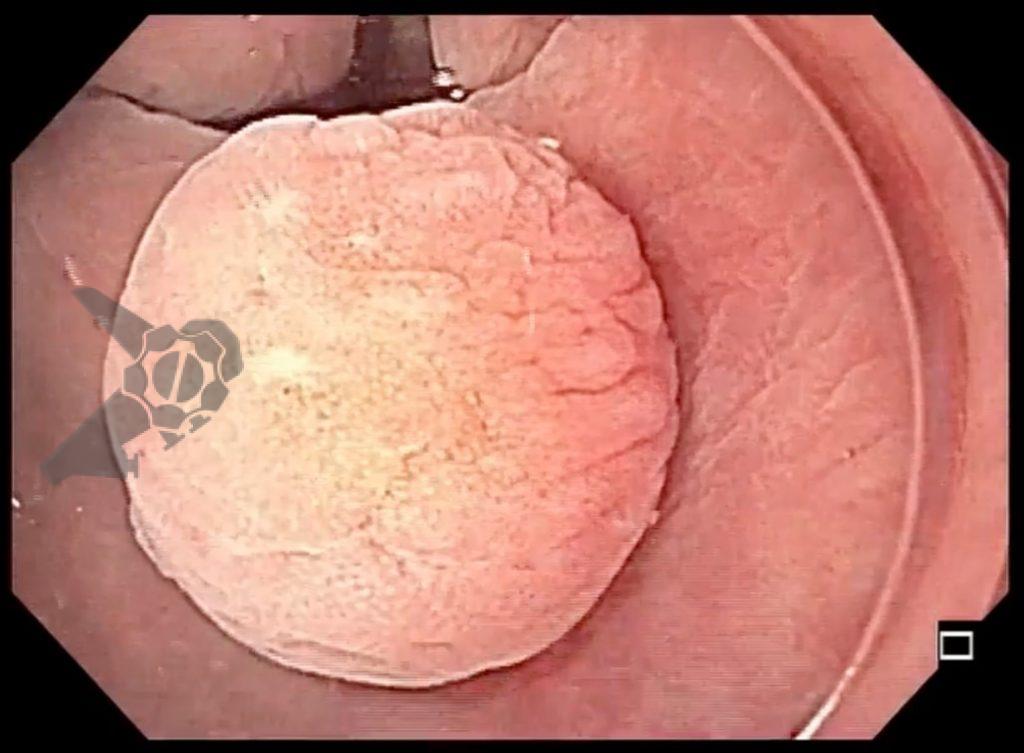

Paciente veio encaminhado para realizar nova colonoscopia na tentativa de ressecção completa da lesão. Durante o procedimento foi observada uma diminuta lesão amarelada no reto, discretamente elevada, correspondente à área de polipectomia prévia com presença de lesão residual (Figuras 1, 2 e 3). Realizada tentativa de mucosectomia pela técnica de imersão (“underwater”), não havendo pega adequada com a alça para ressecção. Foi optado, então, pela realização da mucosectomia por imersão assistida por cap, que consiste na imersão do espaço intraluminal com água, seguido por sucção da lesão com auxílio de cap endoscópico, afim de formar um pseudopólipo, e assim facilitar a apreensão e ressecção da lesão (Figura 4). Com o uso dessa técnica foi possível apreender a lesão residual com a alça e realizar sua ressecção completa (Figuras 5 e 6). O resultado anatomopatológico confirmou a presença de tumor neuroendócrino bem diferenciado (grau 1 – Ki67<2%), com margens laterais e profunda livres.

A mucosectomia underwater assistida por cap (CAP-UEMR) consiste na utilização de cap endoscópico para sucção da lesão a ser ressecada sob imersão em água, até que seja formado um “pseudopólipo” passível de apreensão e ressecção. Se a ressecção em monobloco não for possível, pode-se realizar novos “pseudopólipos” e ressecar à piece-meal, até que se alcance o resultado desejado, conforme ilustrado na figura abaixo: